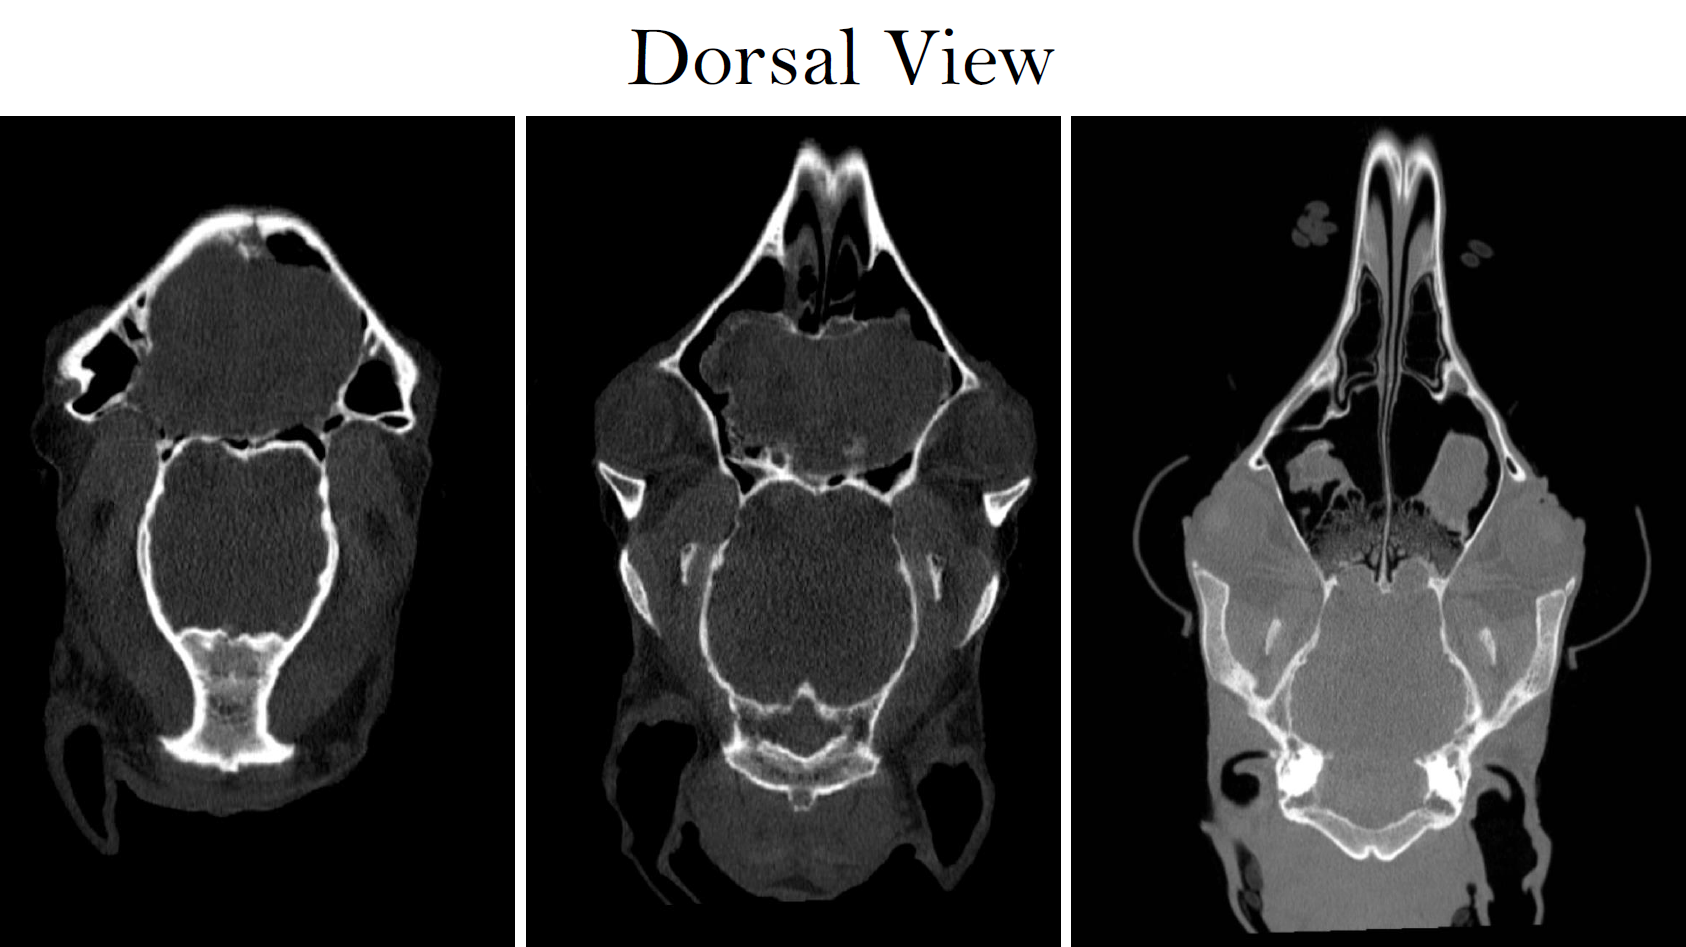

Case Example: 5‑Year‑Old Thoroughbred Gelding, Courtesy of Cotts Equine Hospital

The gelding experienced an acute episode of severe pain followed by collapse and violent thrashing. He had been performing normally prior to the event. Examination revealed grade 3–4 hind‑limb ataxia, with the horse nearly falling when turning. Radiographs and ultrasound did not reveal a cause, prompting CT evaluation.

Presentation

Despite significant ataxia, standing CT successfully imaged the cervical vertebrae through the C5–C6 region.

CT Findings

Findings included:

• Mild funnel-shaped narrowing of the vertebral canal at C4–C5

• Lateromedial elongation and dorsoventral shortening of cranial C4 and C5

• Flattened spinal cord appearance, with loss of surrounding epidural fat

• Moderate dorsal lamina extension (C3–C5)

• Mild endplate flaring (C3–C4)

• Mild periarticular spur formation (C2–C6)

• Mild buttress formation of the right cranial articular process of C6

• Narrow intervertebral disc spaces (C2–C5)

• Reduced intra‑vertebral sagittal ratios at C4 and C5 (<0.50), consistent with cervical canal stenosis

The CT findings provided critical diagnostic information to guide neurologic prognosis and management, clarifying the structural abnormalities contributing to the horse’s severe ataxia.